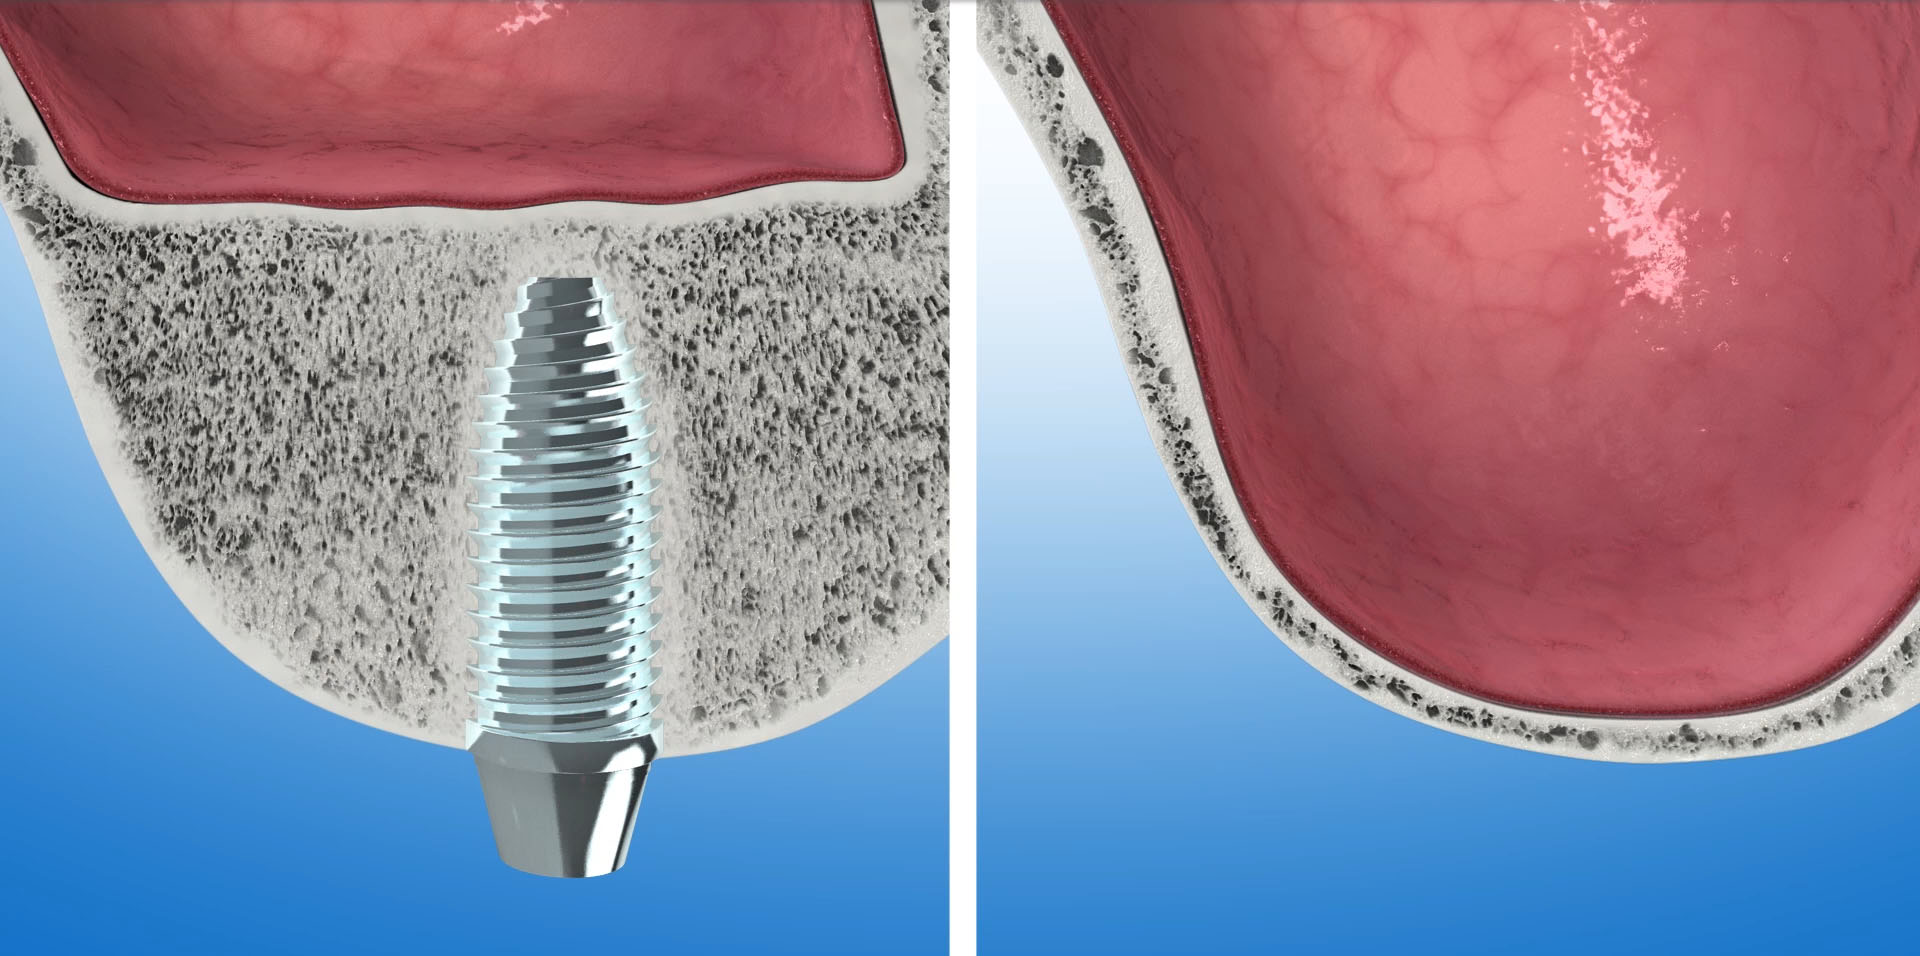

W przypadkach zaniku wyrostka zębodołowego tylko w wymiarze przednio-tylnym, a więc wtedy gdy jest on wystarczająco wysoki lecz bardzo cienki, wąski, zastosowanie znajduje technika zwana rozszczepieniem wyrostka – ridge splitting.

Za pomocą ultradźwięków, kość rozcinana jest wzdłuż szczytu wyrostka, na głębokość ok 1,5-2 cm. Następnie rozcięte blaszki kostne są rozchylane narzędziami ręcznymi. W przestrzeń pomiędzy rozchylone blaszki wyrostka wprowadzamy implanty, które utrzymują uzyskaną szerokość kości. Pozostałe wolne miejsca między rozszczepionymi blaszkami wyrostka uzupełniane są biomateriałem Bio-Oss. Cały obszar zabiegu pokrywany jest na koniec resorbowalna membraną Bio-Gide i zaszywany.

Nacisk rozchylonych blaszek kostnych na implant pozytywnie wpływa na jego stabilizację i przyczynia się do lepszego kontaktu kości z powierzchnią implantu.

Rozszczepienie wyrostka następuje za pomocą ultradźwięków – urządzeniem Surgysonic. Zostaje wprowadzony implant a szczeliny powstałe po rozszczepieniu wyrostka uzupełniane są biomateriałem Bio-Oss.